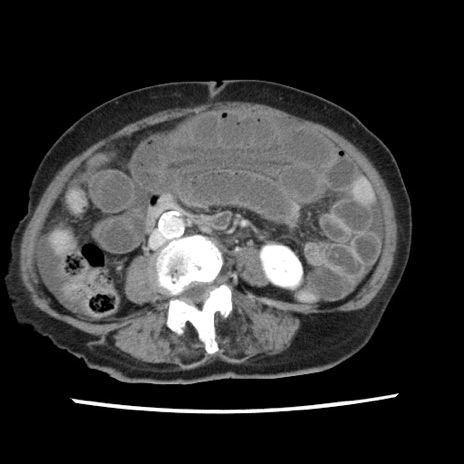

冠状断像

矢状断像

【症例】80歳代女性

【主訴】腹痛

【現病歴】8時間前から腹痛あり来院。

【既往歴】糖尿病、脂質異常症、子宮体癌にて子宮全摘術

【身体所見】意識清明・会話良好だが腹痛で苦悶様、全腹部にわたって反跳痛と圧痛あり

【データ】WBC 13600、CRP 0.14、LDH 224、CK 90